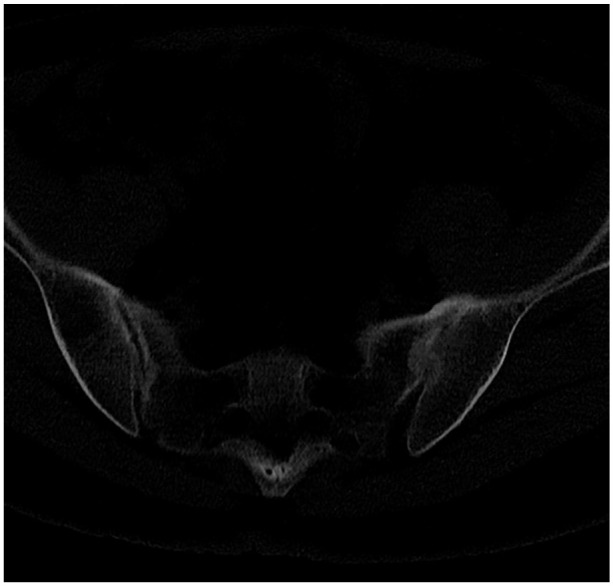

Abstract Image